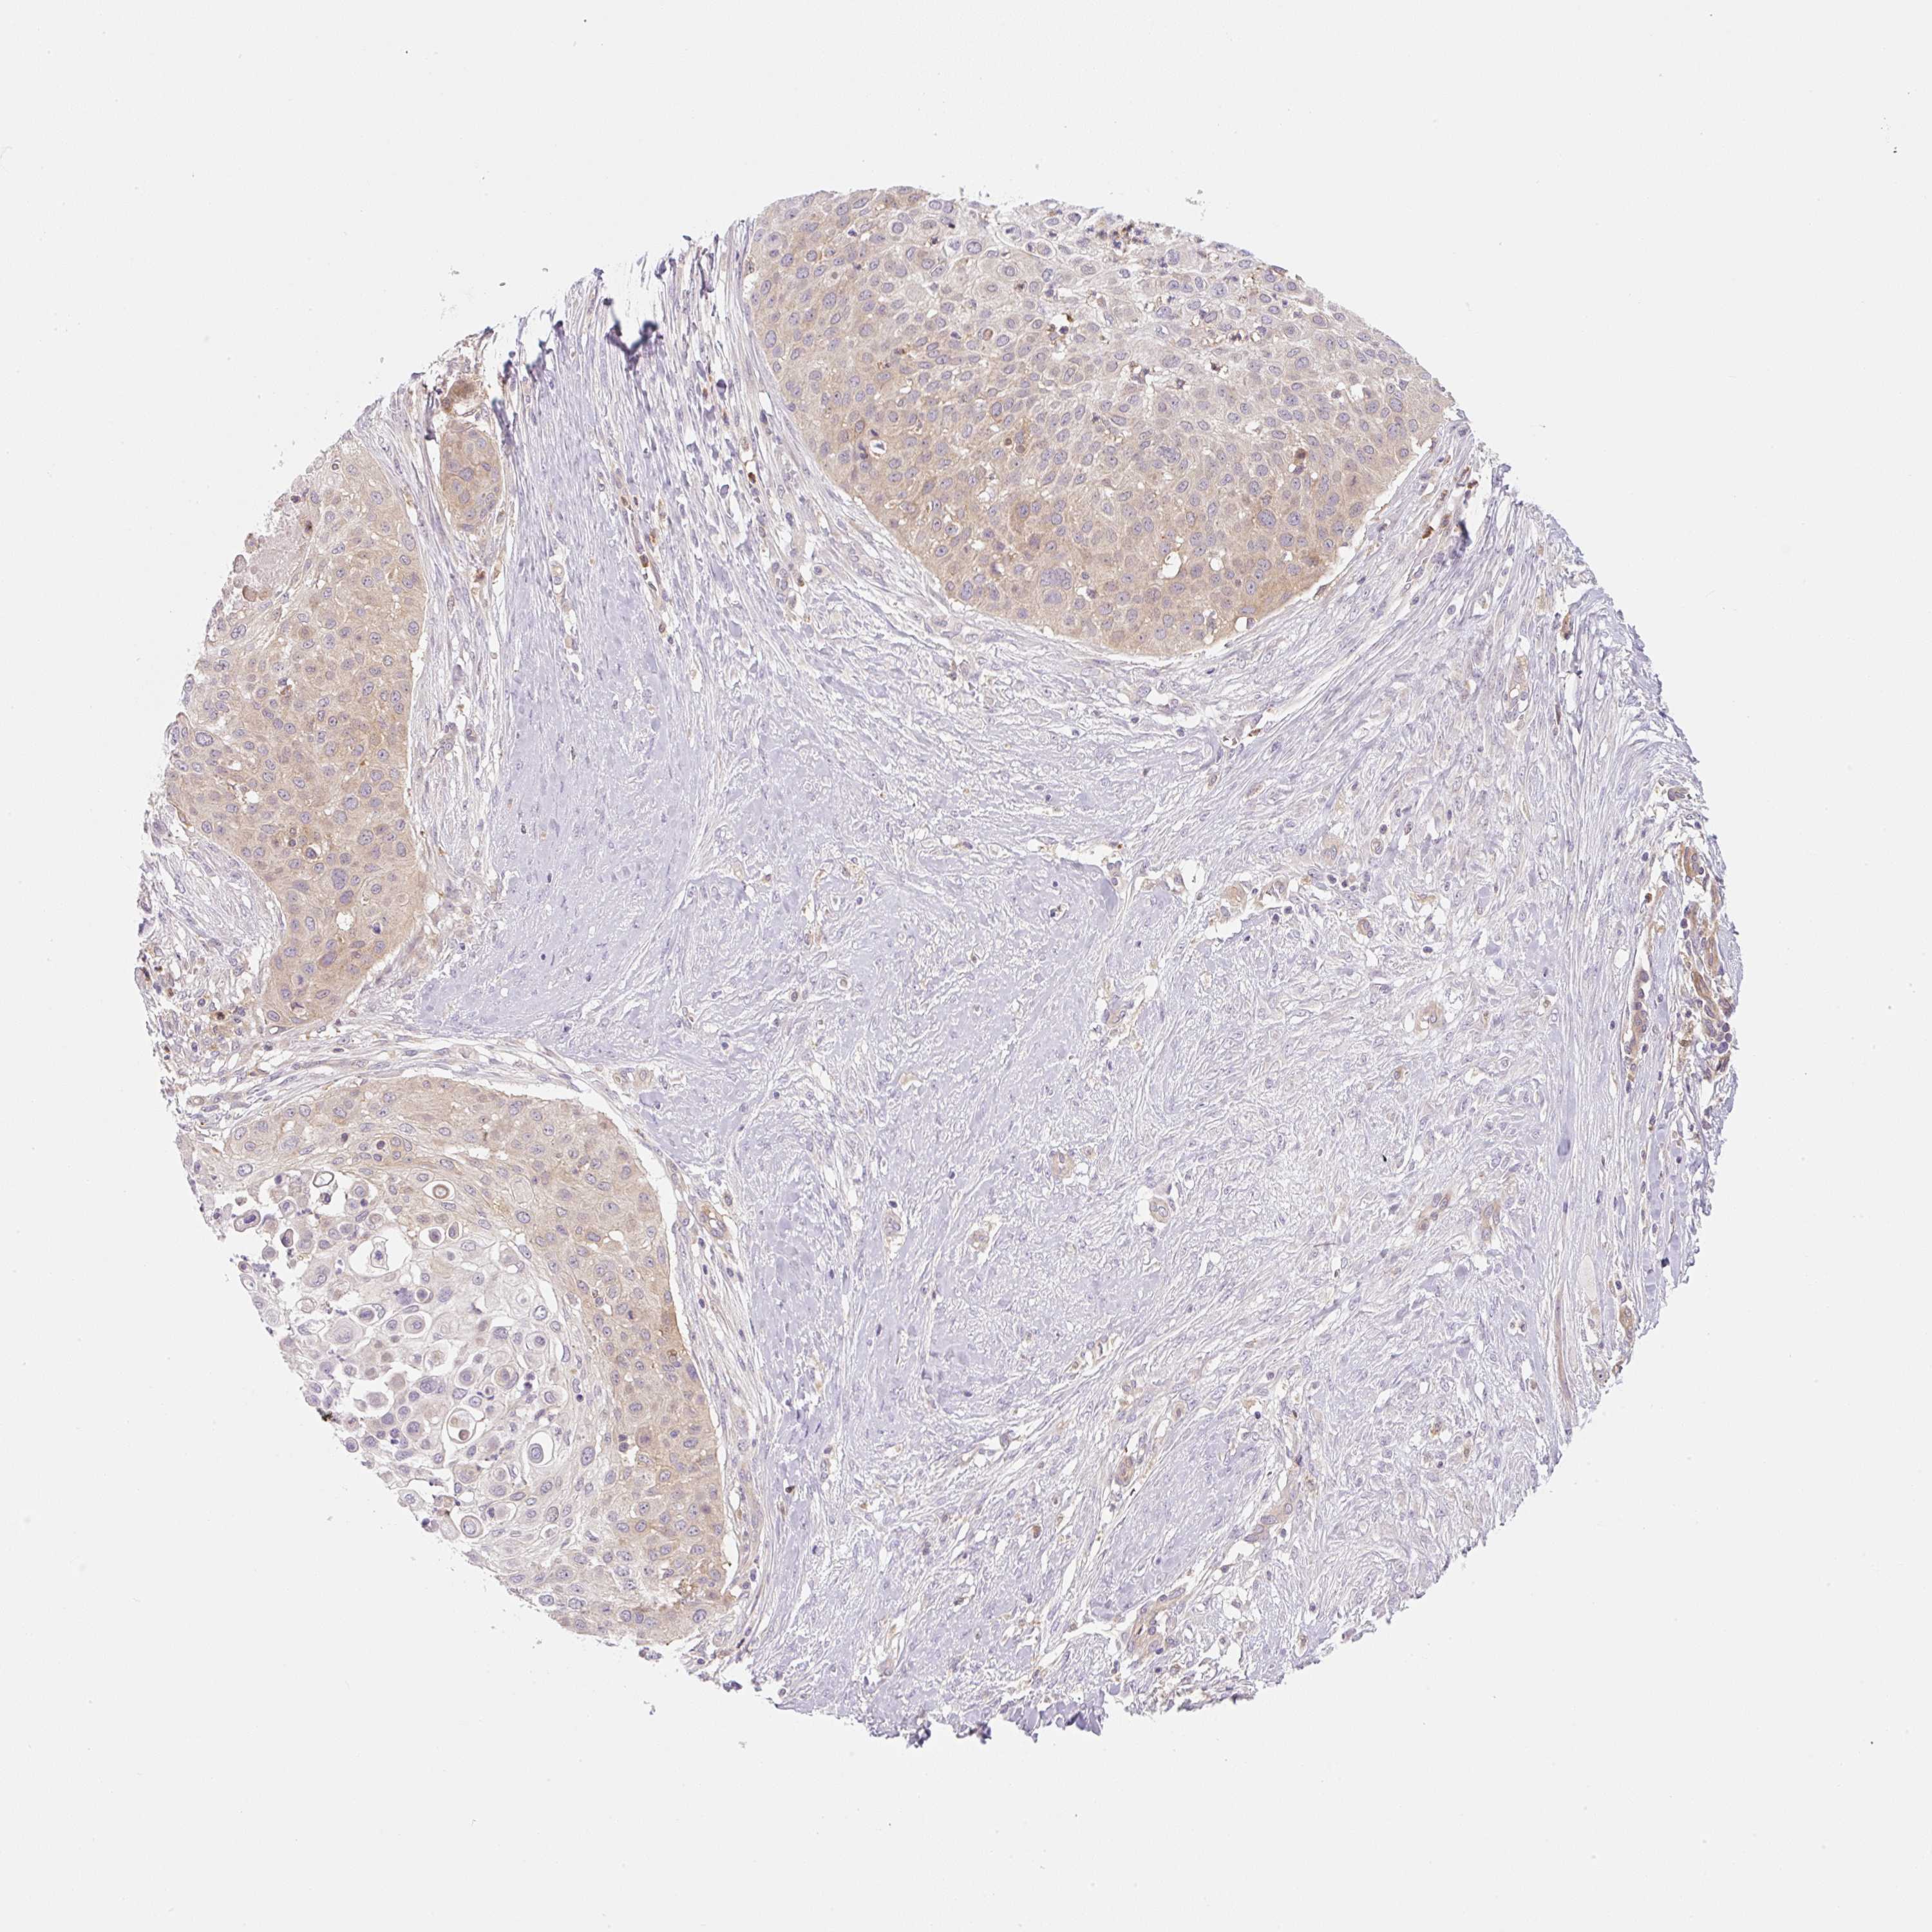

SKIN CANCER - Protein expressioni

A mouse-over function shows sample information and annotation data. Click on an image to view it in a full screen mode. Samples can be filtered based on level of antibody staining by selecting one or several of the following categories: high, medium, low and not detected. The assay and annotation is described here.

Antibody stainingi

Antibody staining in the annotated cell types in the current human tissue is reported as not detected, low, medium, or high, based on conventional immunohistochemistry profiling in selected tissues. This score is based on the combination of the staining intensity and fraction of stained cells.

Each image is clickable and will lead to virtual microscopy that enables deeper exploration of all samples and also displays staining intensity scores, fraction scores and subcellular localization as well as patient and tissue information for each sample.

Antibody HPA055120

Staining

High

Medium

Low

Not detected

Intensity

Strong

Moderate

Weak

Negative

Quantity

>75%

75%-25%

<25%

None

Location

Nuclear

Cytoplasmic/membranous

Cytoplasmic/membranous,nuclear

Basal cell carcinoma

Squamous cell carcinoma, NOS